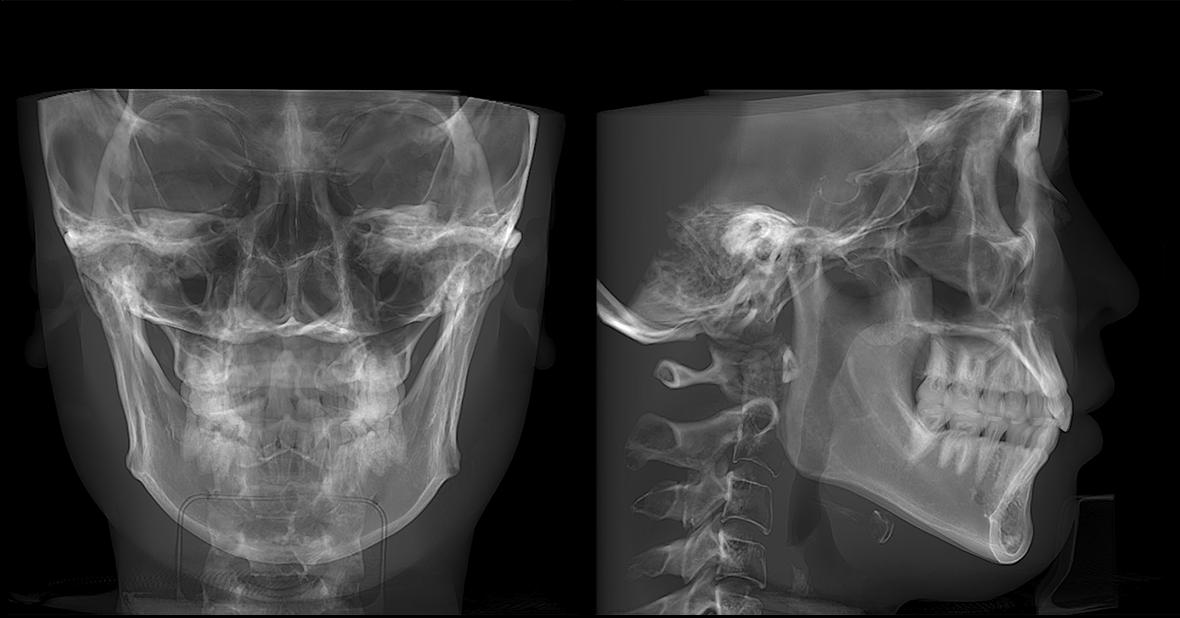

AI 加持,事半功倍 兰台医令的阅片软件包含 AI 神经管绘制、AI 气道分析、AI TMJ分析、AI 牙弓曲线、AI 正畸头影测量等智能图像处理功能,可大大提高诊断效率,实现更好的医患沟通,让医生事半功倍。